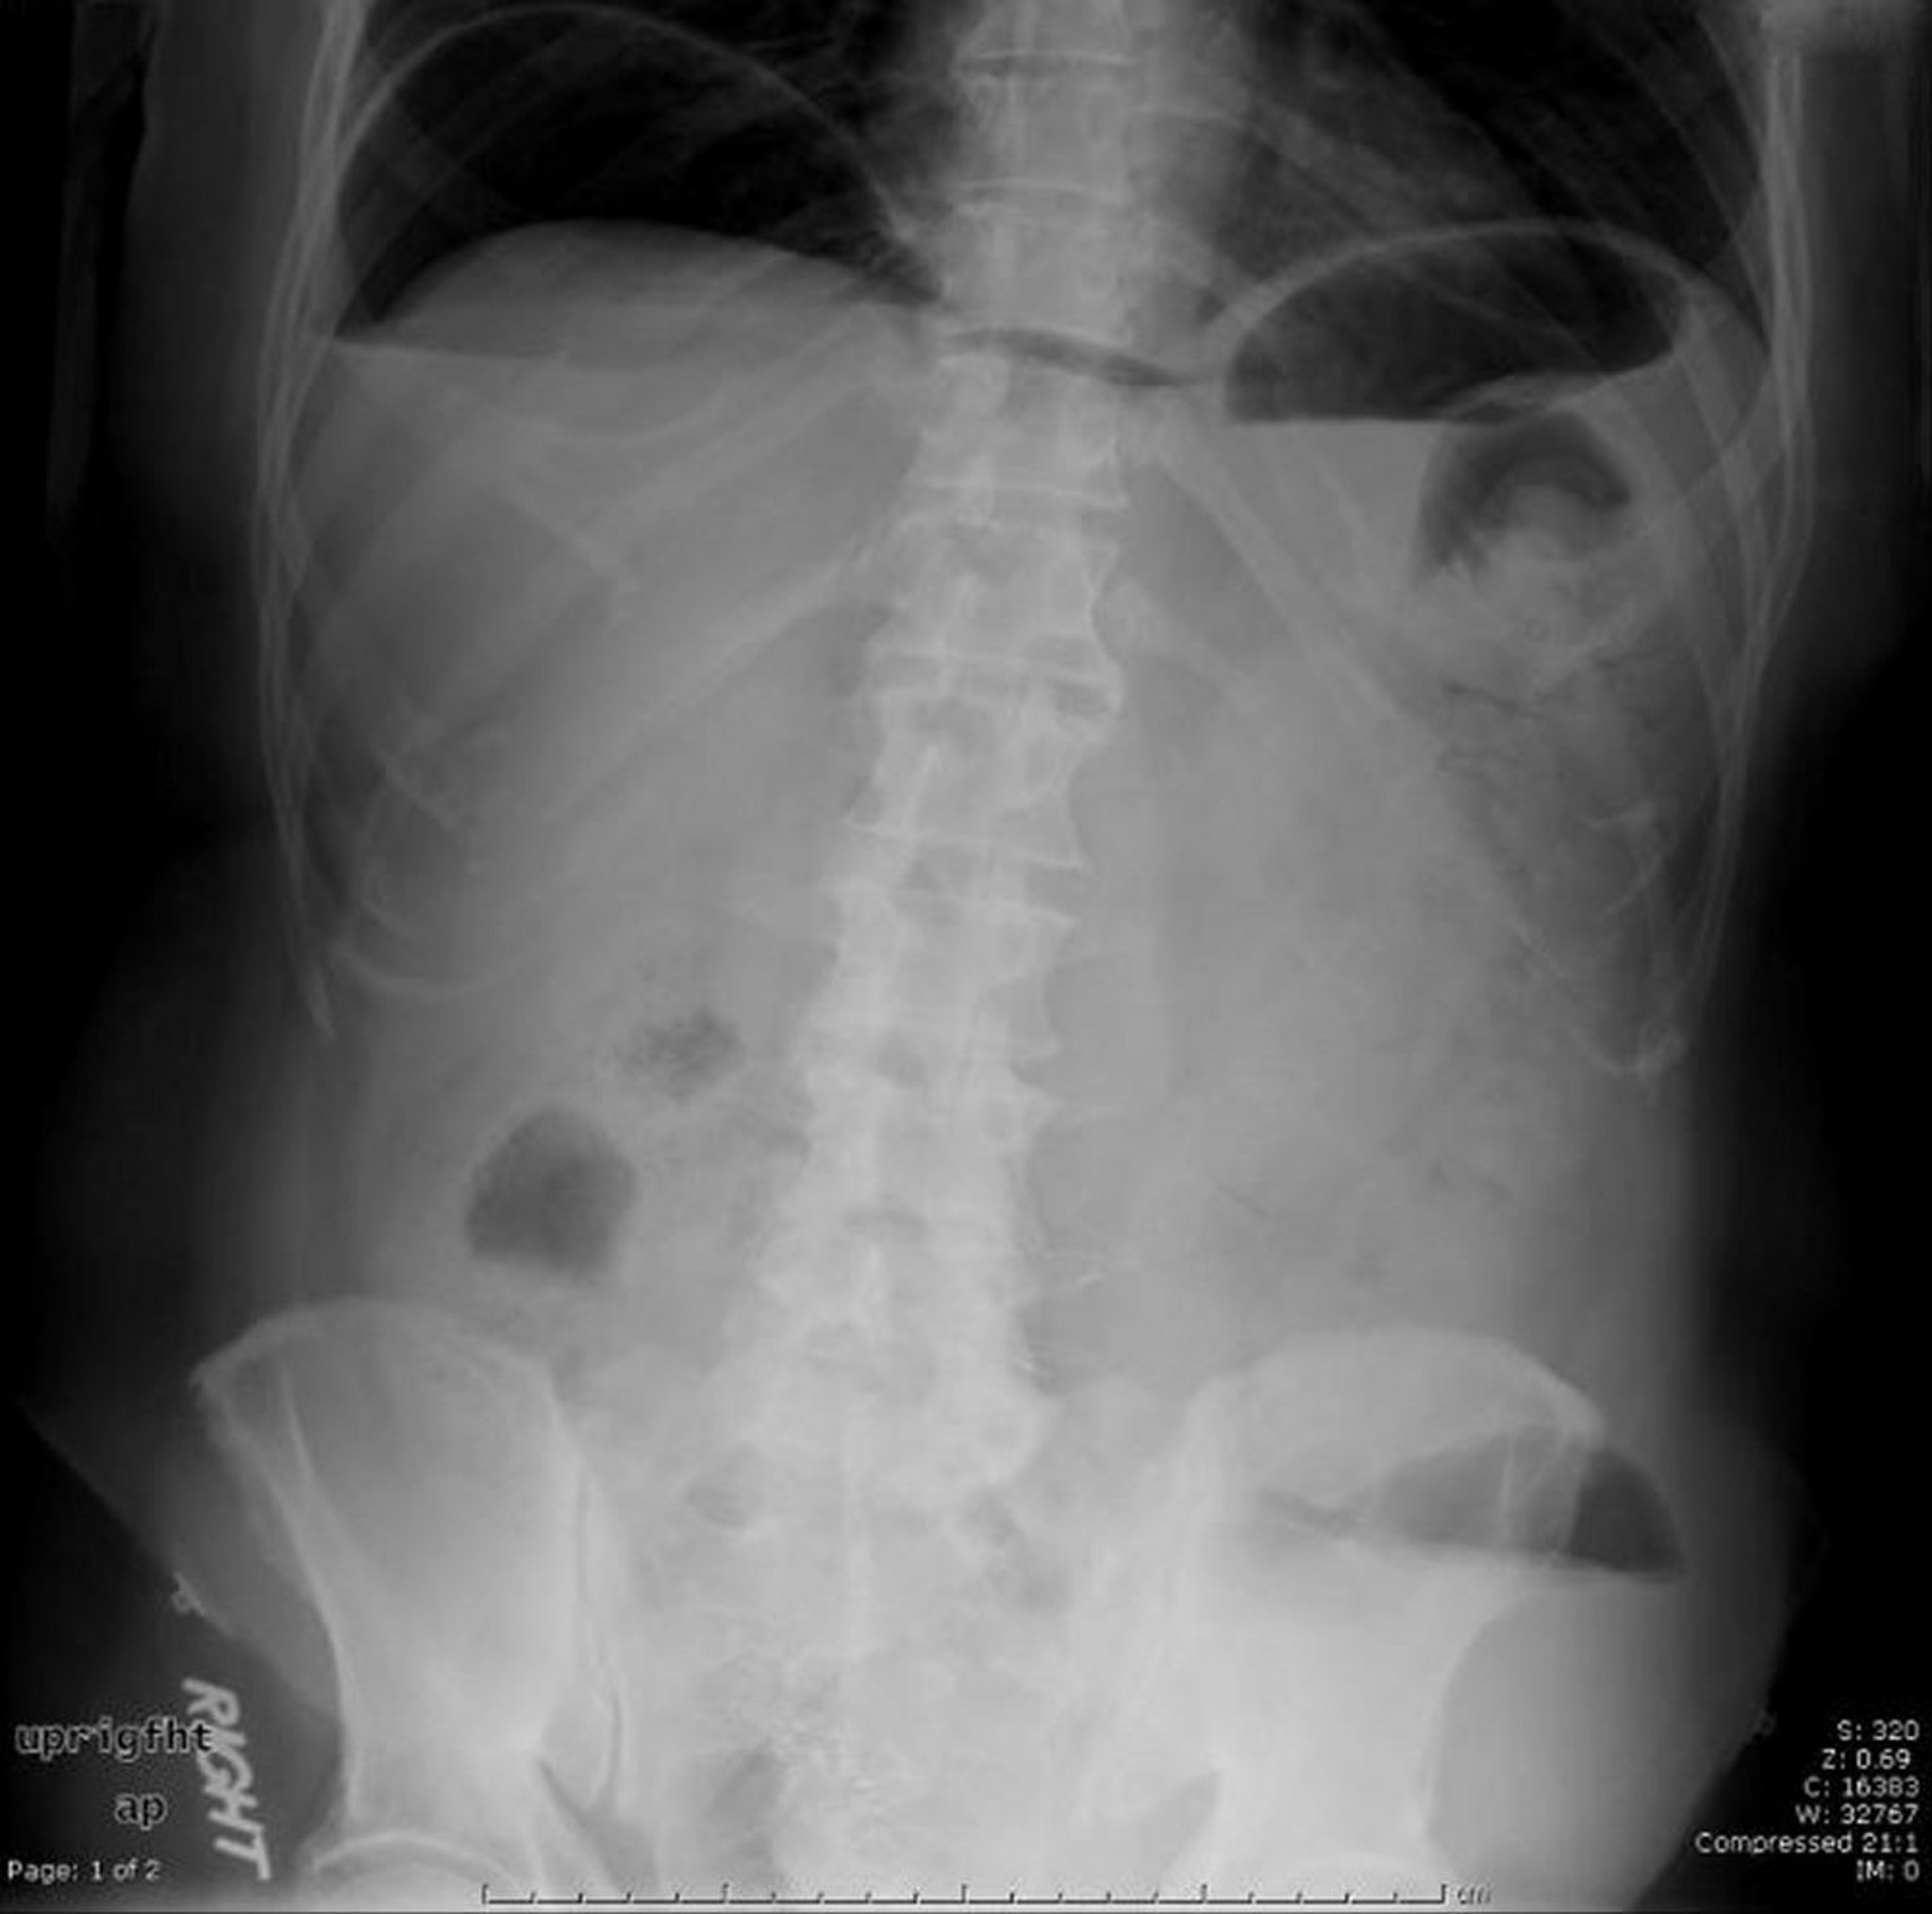

Esta radiografía abdominal muestra aire libre causado por una perforación.

Image provided by Parswa Ansari, MD.